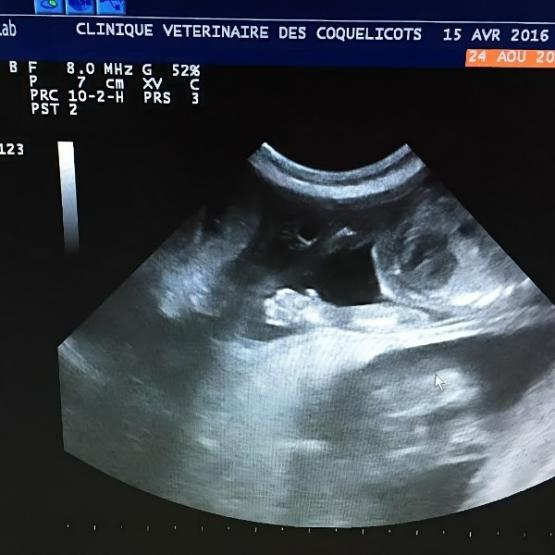

Si nos vétérinaires détectent une anomalie à l'auscultation cardiaque, une échocardiographie pourra être réalisée rapidement dans notre clinique vétérinaire à Saint-Germain-en-Laye, pour identifier rapidement l'étiologie et de mettre en place rapidement un traitement adapté. Pour plus de renseignements sur l'échocardiographie, n'hésitez pas à aller dans la rubrique « Echographie » de notre site internet ou de contacter la clinique aux 01 34 51 90 03.

Parce qu'un malaise cardiaque constitue une urgence vitale, nous sommes équipés pour mettre en place une oxygénothérapie et gérer la douleur de votre animal avant d'établir rapidement l'origine cardiaque et pulmonaire à l'aide d'une échocardiographie réalisée sur place, ainsi qu'un cliché pulmonaire numérique.